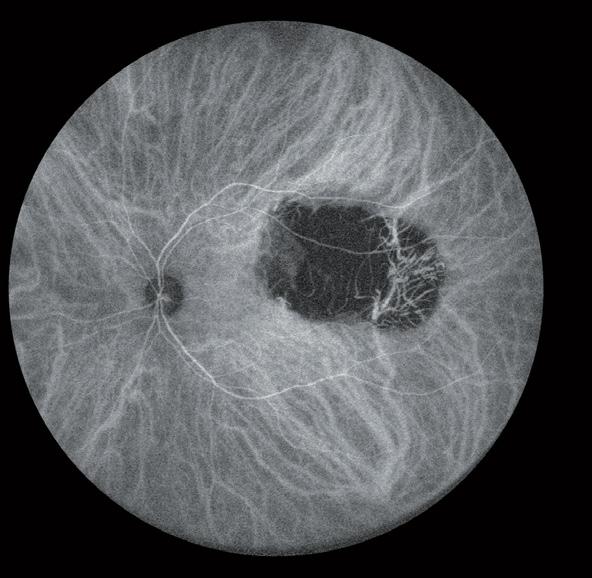

Molecular-scale particles hold promise in new treatments for visual correction. Howard Larkin reports

The multiple lipid, aqueous, mucin and lysozyme-rich layers of the tear film and cornea are highly effective at keeping irritants and pathogens out of the eye. The trouble is, they are nearly as effective at keeping out topical drugs – only 5-to-10% administered typically reach the anterior chamber, David Smadja MD told the 37th Congress of the ESCRS in Paris, France.

Similarly, the sclera blocks topical drugs from the retina and vitreous while the blood-retinal and retinal pigment epithelium barriers restrict systemic drugs. That leaves invasive injections and intravitreal depots as the most effective administration routes for back-of-the-eye treatments, and these are subject to rapid chemical breakdown, added Dr Smadja, who directs and conducts research at Shaare Zedek Medical Centre, Jerusalem, and Bar-Ilan University, Ramat Gan, Israel.

Nanotechnology could change that, Dr Smadja believes. Nanosystems measuring 300nm or less – about three times the diameter of the HIV virus – may overcome problems that reduce drug efficiency by combining and layering even smaller nanoparticles – of 1-to-100nm – with varying chemical, electrical, biologic and physical characteristics. Together, these may be designed to address major challenges in anterior and posterior drug delivery, including drug washout, lack of penetration and enzymatic destruction.

The promise of nanoparticles the ECCTR

Adding positively charged mucoadhesive particles, such as chitosan, to the surface of a nanocapsule could greatly increase residence time in the precorneal space by sticking to the negatively charged posterior layer of tear film (mucine layer), Dr Smadja said. This allows more time for smaller drug particles in the capsule to penetrate the corneal epithelium, reducing washout. Residence time could be further enhanced by placing nanocapsules in a hydrogel matrix or contact lens placed on the ocular surface.

On the corneal surface, nanocapsules could slowly release even smaller capsules coated with lipophilic material designed to move hydrophilic drugs through the lipid-rich epithelium and endothelium. Materials such as hyaluronic acid-chitosan nanoparticles have successfully penetrated cell barriers.

“It’s the old trick we all know, the Trojan horse, where you encapsulate the drug in something that looks friendly,” Dr Smadja said.